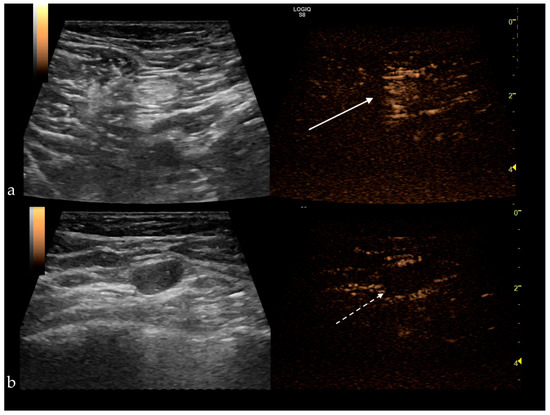

Type I was considered benign, types II and III were deemed malignant (Figure 4), yielding a sensitivity (Se) of 100%, a specificity (Sp) of 52%, with a positive predictive value of 64.9%, negative predictive value of 100% and a diagnostic accuracy of 64.9%. Therefore, the homogeneous enhancement has the highest negative predictive value, representing an indicator of benignity. In contrast, inhomogeneous or no enhancement is due to perfusion defects and is significantly associated with lymph node tumor infiltration [50,52]. The sentinel node’s heterogeneous appearance was observed in the case of Her2 positive tumors and in tumors ≥2 cm [9,29,33].

Figure 4. (a) Benign sentinel lymph node presenting a homogenous central enhancement (white arrow); (b) Metastatic sentinel lymph node with no enhancement after subcutaneous administration of the contrast agent (white dotted arrow).